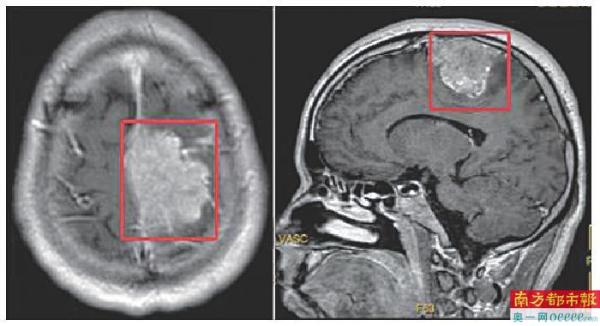

磁共振显示的巨大肿瘤已达5.6厘米。

在医院做头颅磁共振检查提示:“左侧顶部颅内脑外实性肿块,压迫上矢状窦”,也就是说小王的脑袋里长了个矢状窦旁脑膜瘤,直径达5.6cm。而小王之所以走路会“掉鞋”,就是因为肿瘤压迫到了神经,导致肢体偏瘫、感觉障碍。龙华区人民医院神经外科主任刘诤告诉他,只能手术切除。近日,刘诤带领团队成功切除肿瘤,术后小王恢复良好,目前已痊愈出院。